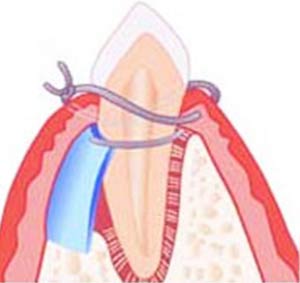

بازسازی هدایت شده بافت لثه

این تکنیک جراحی لثه با تحریک رشد بافت لثه و استخوان عمل میکند. پس از فلپ کردن (بلند کردن) لثه از روی استخوان، یک تکه پارچه توری کوچک بین بافت لثه و استخوان قرار میگیرد. این اقدام به جلوگیری از رشد بافت لثه در فضایی که لازم است استخوان در آن رشد کند کمک میکند و برای استخوان و بافتهای متصل به آن، این امکان را فراهم میکند تا رشد یافته و در نتیجه از دندان پشتیبانی کند.